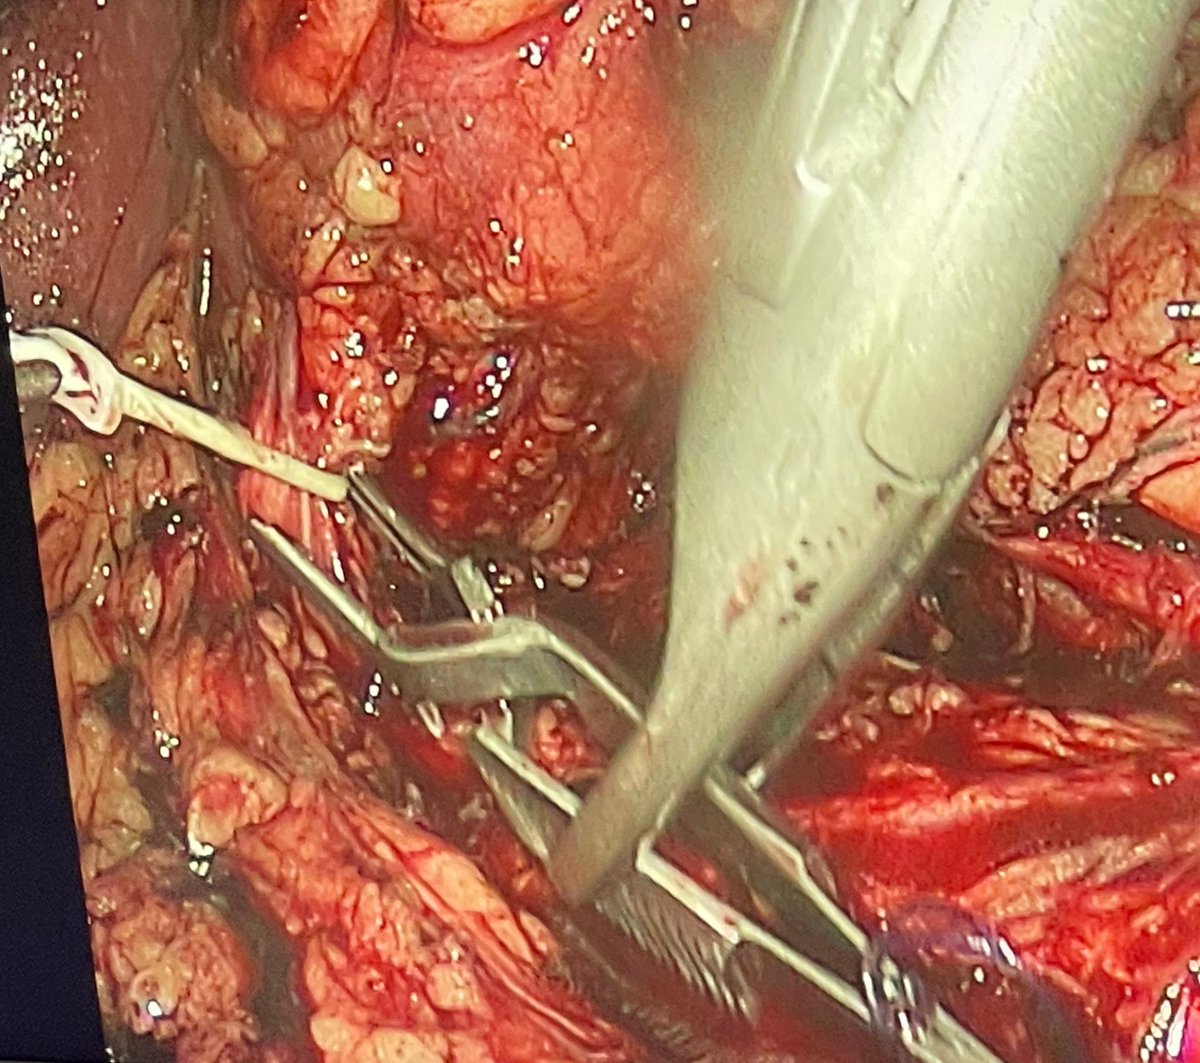

Dr Fouad Zanaty

Professor of Urology